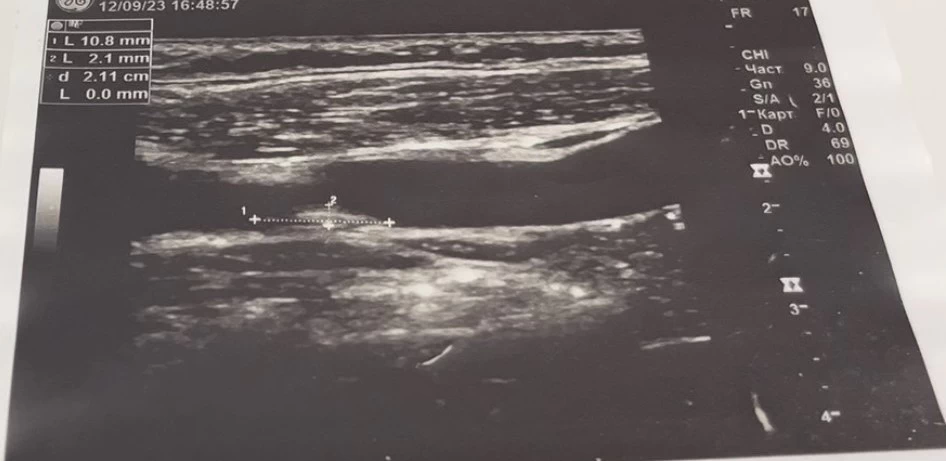

Заподозрить наличие варикозной болезни нижних конечностей может любой врач при проведении планового или целевого осмотра. Терапевт, хирург, гинеколог, кардиолог или даже дерматолог, заметив характерные внешние проявления — телеангиэктазии, ретикулярную сеть, извитые подкожные вены, отёчность или изменения кожи — могут ориентировать пациента для углублённого обследования. Однако констатация визуальных признаков является лишь предварительным этапом.

Полноценно обнаружить, детально описать и дать гемодинамическую оценку всем венам (поверхностным, глубоким, перфорантным) способен только врач ультразвуковой диагностики, владеющий методикой сканирования вен.